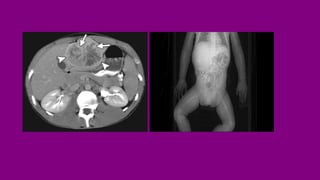

RADIOLOGY

❖ CT scan-is the imaging of choice in

preoperative diagnosis and

staging. Pelvis, chest, abdomen,

❖ MRI :liver help to stage the patient

❖ PET-CT with fluorodeoxyglucose (F-

FDG) optimizes anatomical

localization of the lesions and

response to treatment